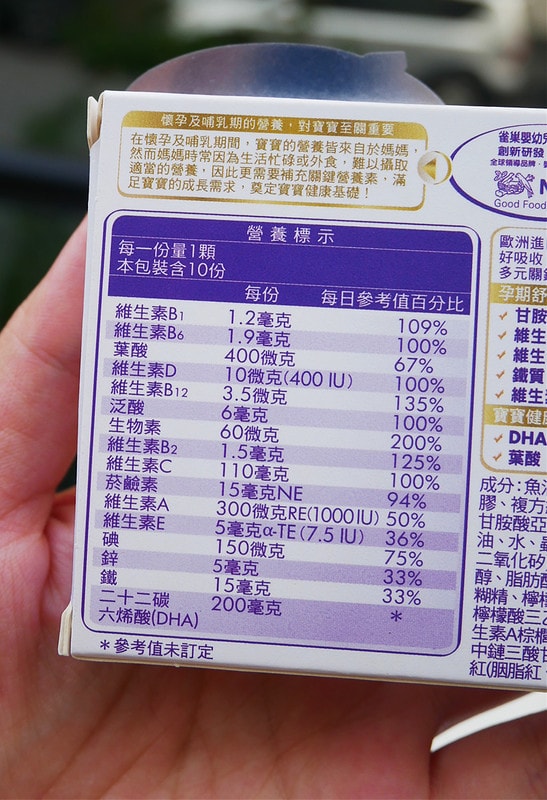

雀巢媽媽膠囊體驗組長這樣

一盒裏頭有十顆

營養標示包裝上都寫得很清楚喔

比方說孕期最需要的鐵、DHA、葉酸、綜合維生素等

裏頭都有包含到唷

一顆裡面有葉酸、B群等綜合維他命、足量DHA、甘胺酸亞鐵等孕期關鍵營養,

甘胺酸亞鐵的突破性科技,更可以輕鬆幫助鐵質攝取

可滿足各階段關鍵營養需求,適合備孕、懷孕初、中、晚期以及哺餵母乳的媽媽。”